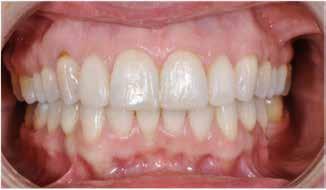

Patienttilfælde 1 (Fig. 1) er en 37-årig kvinde, henvist efter succesfuld behandling af stadie 3-parodontitis. Der er nu sundt

Før behandling

parodontium, ingen pocher over 4 mm, og både blødnings- og plakindeks er under 10 %. Patienten er motiveret for ortodontisk behandling, da hendes tænder er vandret over tid, delvist som følge af reduceret parodontium.

Der ses anterior trangstilling i begge kæber og overerupterede 1+1 og 2,1-1,2, hvilket resulterer i dybt bid med 2- tæt på ganepåbidning. Der er normale sidetandsrelationer, men der ses 5 mm horisontalt overbid (HOB) og 7 mm vertikalt

overbid (VOB). Papillen mellem 1+1 er betydeligt reduceret pga. fæstetab, og de mesialt kippede 1+1 har resulteret i en ”dark triangle”. Den facioorale funktion er for nuværende i.a. Panoramarøntgen (Fig. 1, I) viser marginalt knogletab i begge kæber og fravær af 8,7+7,8 og 8,7-8.

Der planlægges alignerbehandling af begge kæber med intrusion af 1+1 og 2,1-1,2, nivellering af trangstilling UK med interproksimal reduktion (IPR) (Fig. 2 A, B) og senere IPR OK for reduktion af dark triangles mellem incisiverne efter nivellering. Patienten instrueres i at benytte alignere 20-22 timer/ dag med alignerskift hver 7. dag, og patienten ses hver 3.-8. uge under forløbet. Den første alignerserie består af 16 alignere for nivellering OK/UK og IPR i UK (Fig. 2). Efter denne serie planlægges IPR mellem incisiverne i OK for reduktion af dark triangles (Fig. 3) samt yderligere intrusion af OK og UK-fronten i 12 refinement-alignere. Patienten udviser god kooperation og er meget tilfreds med alignerapparaturet, som er mindre synligt end det faste apparatur (Fig. 4).

Behandlingen afsluttes med yderligere refinement-alignere for finindstilling af okklusionen, og efter 11 måneders ortodontisk behandling er der opnået normale relationer i alle tre